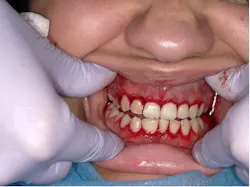

A 17-year-old female presented to a dental school clinic with a chief complaint of a sudden, painless swelling of her gingivae (figures 1 and 2).